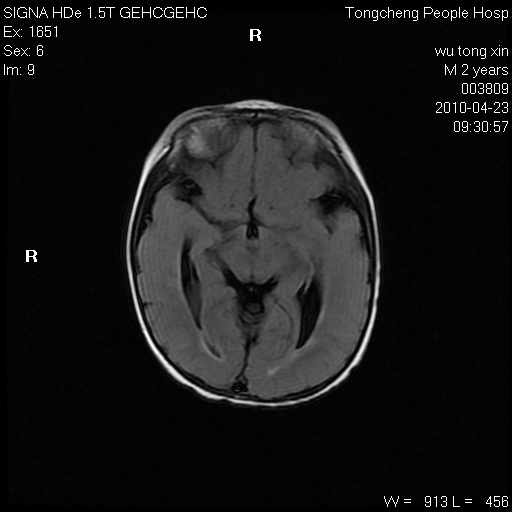

以下是引用赵物学在2010-4-25 12:43:00的发言:[br]巨脑回[br]侧脑室后角低密度影考虑hie或肾上腺脑白质营养不良?[br][br][本贴已被 赵物学 于 2010-4-25 12:51:28 修改过]

以下是引用gaoxiao在2010-4-25 16:54:00的发言:[br]巨脑回畸形。脑白质髓鞘化不良

以下是引用pujunzhi在2010-4-25 21:35:00的发言:[br]考虑 1双侧大脑皮质发育不良 2轻度脑积水 3双侧脑室后角旁片状长t1长t2信号,需继续观察,因为正常小儿此处脑白质的髓鞘化时间可以延迟到4-6岁,才显示正常。